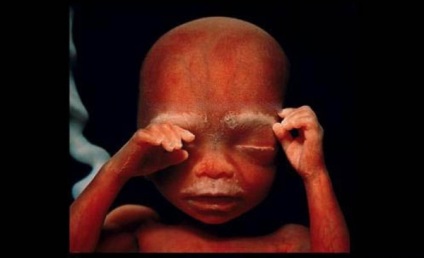

10 săptămâni. Pleoapele sunt deja pe jumătate deschise. În termen de câteva zile, acestea vor forma complet.

10 săptămâni. Copilul este deja cu mâinile sale pentru a explora zona